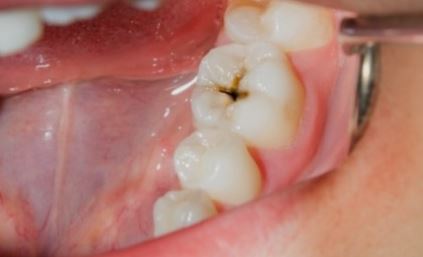

저희 조카는 치아에 충치가 좀 있는 편인데, 최근에 아기 치아우식증 때문에 많이 힘들었다고 해요. 우리가 매일 음식을 먹고 살아가는데 치아 표면에 음식찌꺼기 등이 붙어서 세균이 만들어지고, 치아를 파괴하는 치아우식증은 감염성 질환입니다. 그런데 아기를 키우다보면 한번쯤 들어보셨을 아기 치아우식증이나 충치, 착색, 변색 대해서 한번 알아보고자 합니다.

주기적으로 영유아 치과검진을 하게 될텐데 아기 치아를 살펴보다가 착색 또는 충치처럼 보이는 것들이 있습니다. 치아관리를 소홀히 하면 부정교합이나 나중에 영구치가 난 후에도 치주질환 때문에 고생할 수가 있어서요. 유치때부터 아기 충치 착색 우식증 예방을 위한 노력과 관리는 꾸준히 해주어야 합니다.

치아표면의 플러그 때문에 겉면이 손상되고, 아기 스스로 양치하라고 내버려두었을 때 양치가 제대로 되지 않아서 치아우식증이 대부분 발생합니다. 흰색 반점 또는 띠가 보이기도 하고, 치아표면이 깨져나가기도 하고, 치통이나 고름이 나는 우아기 치아우식증의 형태들을 살펴볼 수 있습니다.

- 가장 흔한 우식증 증상은 처음에 하얀반점처럼 띠가 생기는 증상입니다. (이후 이가 깨져나가게끔 진행)

그냥 소홀히 지나칠 수도 있는데 빠르게 착색이나 반점을 확인한다면 우식증을 초반에 치료할 수가 있는데요. 스스로 양치를 잘 못하는 아기들을 위해서 엄마가 항상 옆에서 케어해주세요. 치과에 갔는데 자세히 살펴보면 생각보다 치료할 이빨이 많아서 부모님은 놀라게 된답니다.